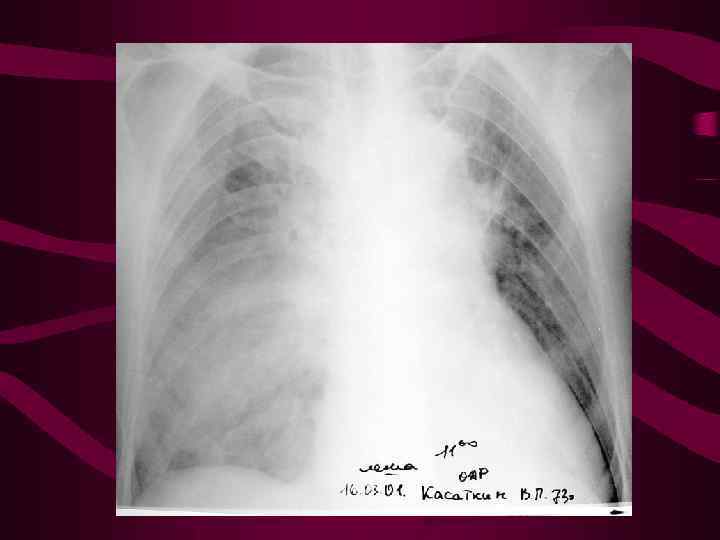

4 - альвеолярный отек легких Изменения соответствуют среднему давлению в левом предсердии свыше 35 мм рт. ст. На фоне венозного застоя с признаками интерстициального отека определяются множетсвенные сливающиеся, разной величины очаговые тени в легких за счет скопления эксудата в альвеолах. Очаговость имеет неравномерную интенсивность и нечеткие очертания, может быть симметричной, двухсторонней, но может быть и односторонней. Нередко выпот в плевральных полостях.

4 - альвеолярный отек легких Изменения соответствуют среднему давлению в левом предсердии свыше 35 мм рт. ст. На фоне венозного застоя с признаками интерстициального отека определяются множетсвенные сливающиеся, разной величины очаговые тени в легких за счет скопления эксудата в альвеолах. Очаговость имеет неравномерную интенсивность и нечеткие очертания, может быть симметричной, двухсторонней, но может быть и односторонней. Нередко выпот в плевральных полостях.

Альвеолярный отек слева

Альвеолярный отек слева